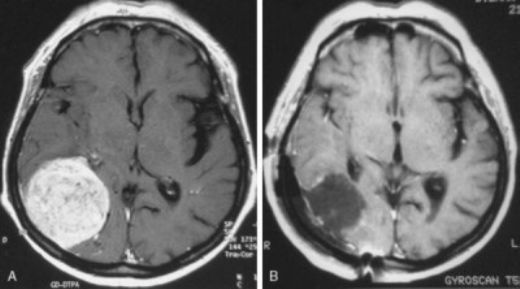

Beyine metastaz yaptığında şiddetli baş ağrıları ve hafıza karışıklıkları yaşanmasının nedeni, beyindeki artmış basıncın ve beyin dokusuna olan hasarın bu tür belirtilere yol açmasıdır. Beyin dokusu hassas olduğu için, metastazlar burada ciddi belirtiler yaratabilir. Bu nedenle, bu tür belirtiler görüldüğünde hemen bir doktora başvurmak önemlidir.